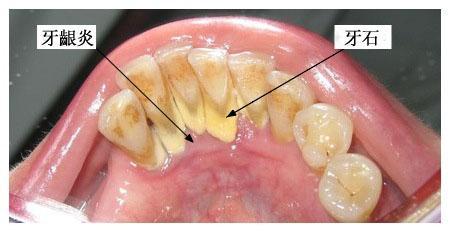

牙齦炎是一種最常見(jiàn)的牙齦疾病,多為牙菌斑引起的牙齦軟組織的非特異性炎癥。

由于牙齦炎無(wú)深層牙周組織的破壞,通過(guò)洗牙一般可徹底清除菌斑、牙石,消除造成菌斑滯留和局部刺激牙齦的因素,炎癥均可消退,一般一個(gè)星期就可恢復(fù)到健康的牙齦狀態(tài)。

牙齦炎是牙菌斑和牙結(jié)石引起的慢性炎癥,發(fā)炎的時(shí)候吃甲硝唑和頭孢。平時(shí)多喝貝齒寧茶,消菌殺毒,早晚刷牙。使牙齒縫間和齒齦之間的牙刷清洗不到的地方清理干凈,保持口腔內(nèi)的酸堿平衡 堅(jiān)持使用2-3周后刷牙出血癥狀會(huì)停止,腫痛不再。炎癥消退后,去牙醫(yī)診所去洗牙,把牙結(jié)石徹底清理,平日再堅(jiān)持口腔護(hù)理,就可以沒(méi)有口臭,炎癥消退,牙齦不腫痛,刷牙不出血了。平時(shí)護(hù)理: